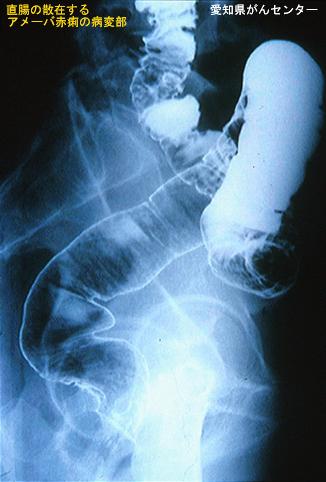

A case of intestinal amebuiasis associated with early sigmoid colon cancer.

Aichi Pref., Aichi Cancer Center

Inflammatory or ulcerative disease / lesions/Amebiasis

Large intestine(Colon)/Rectum

X-ray